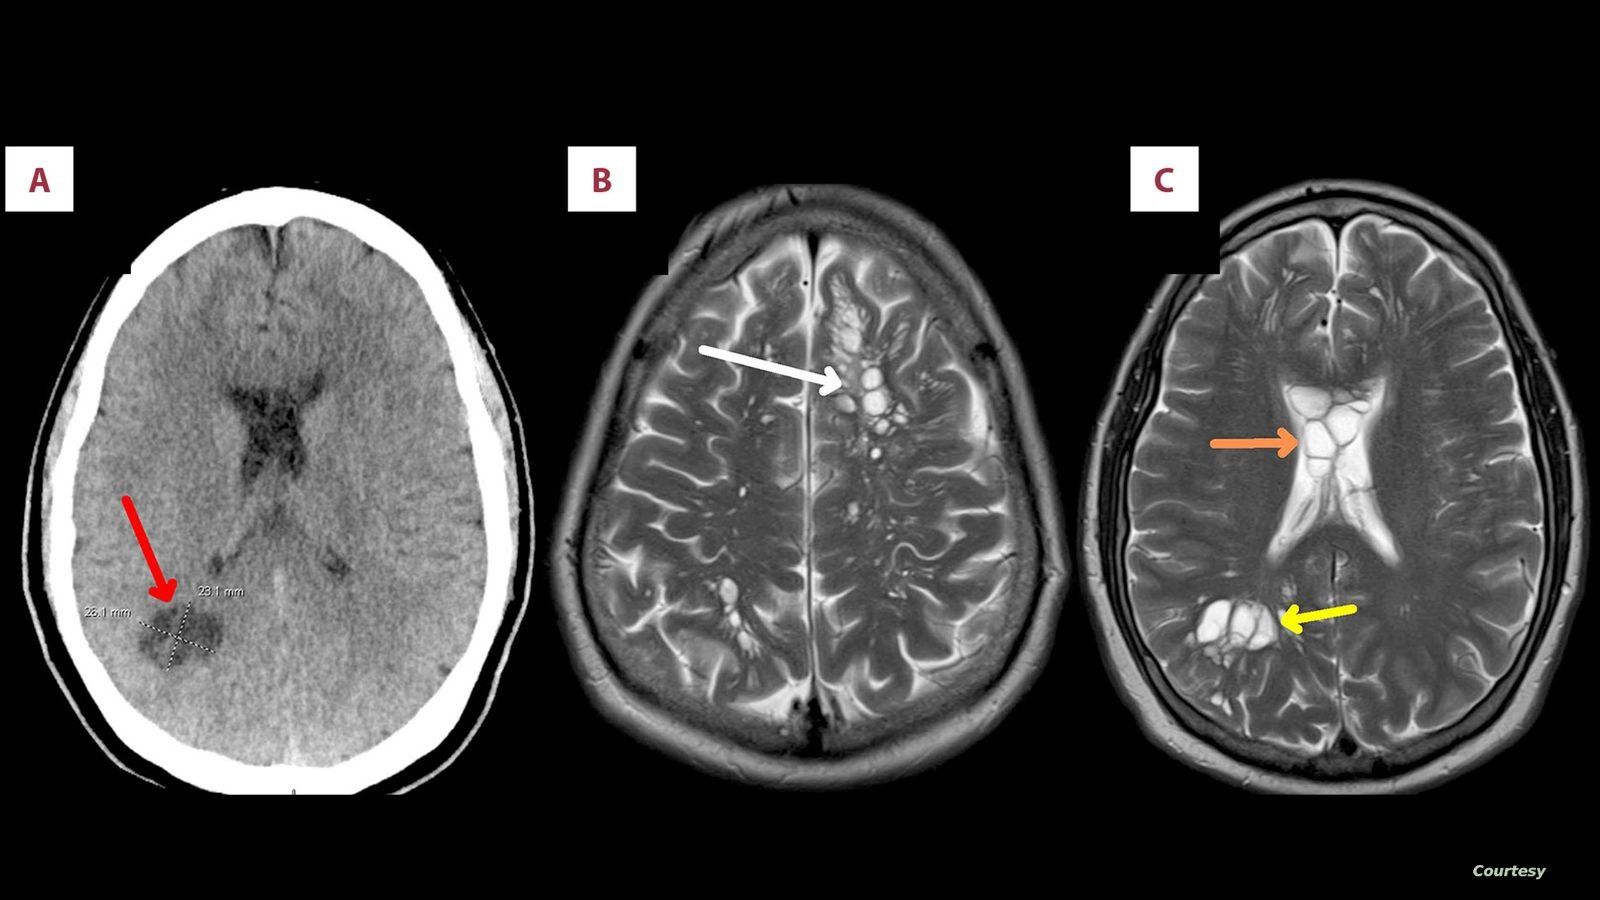

وكشف تصوير بالأشعة المقطعية أجراه أطباء لدماغ الرجل، عن بيوض الدودة الشريطية، وتم تشخيص المريض بداء الكيسات المذنَّبة العصبي.

وذلك الداء هو نوع خاص من داء الكيسات المذنبة، يحدث بسبب عدوى بالشريطية الوحيدة، وهي شريطية حقيقية (Eucestoda) تُوجد في الخنازير، والتي يمكن أن تصل إلى الأنسجة مثل العضلات والدماغ.